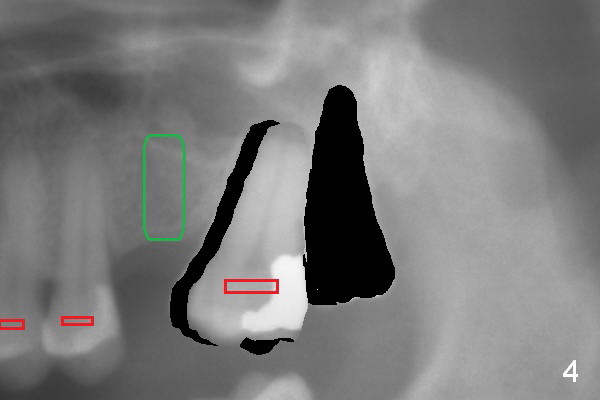

When the tooth #15 is distalized (Fig.3), place an implant at #14 (Fig.4 green), parallel to the tooth #13 and extract #16 (black). When the implant osteointegrates, place an abutment (Fig.5 pink), provisional (white) and bracket at #14. The implant is used as an anchorage to further distalize #15 until the latter reaches the normal position (Fig.6). CT study shows how much the tooth movement is needed prior to implantation.